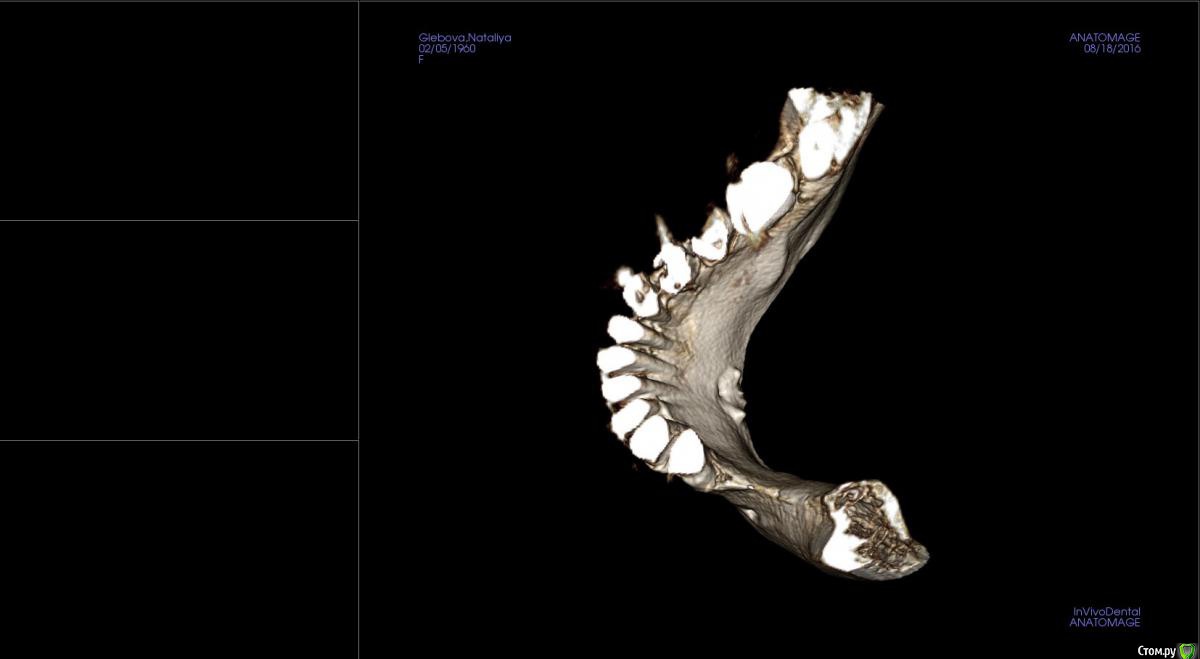

kamranchick Опубликовано 23 августа, 2016 Поделиться Опубликовано 23 августа, 2016 Господа, как посоветуете поступить на 4 сегменте?Какая методика здесь будет предсказуема, и возможно ли установка сразу болтов, так как пациентка уезжает на 8 месяцев в командировку, смущает что менталис рядом и очень тоненький биотип десны Ссылка на комментарий